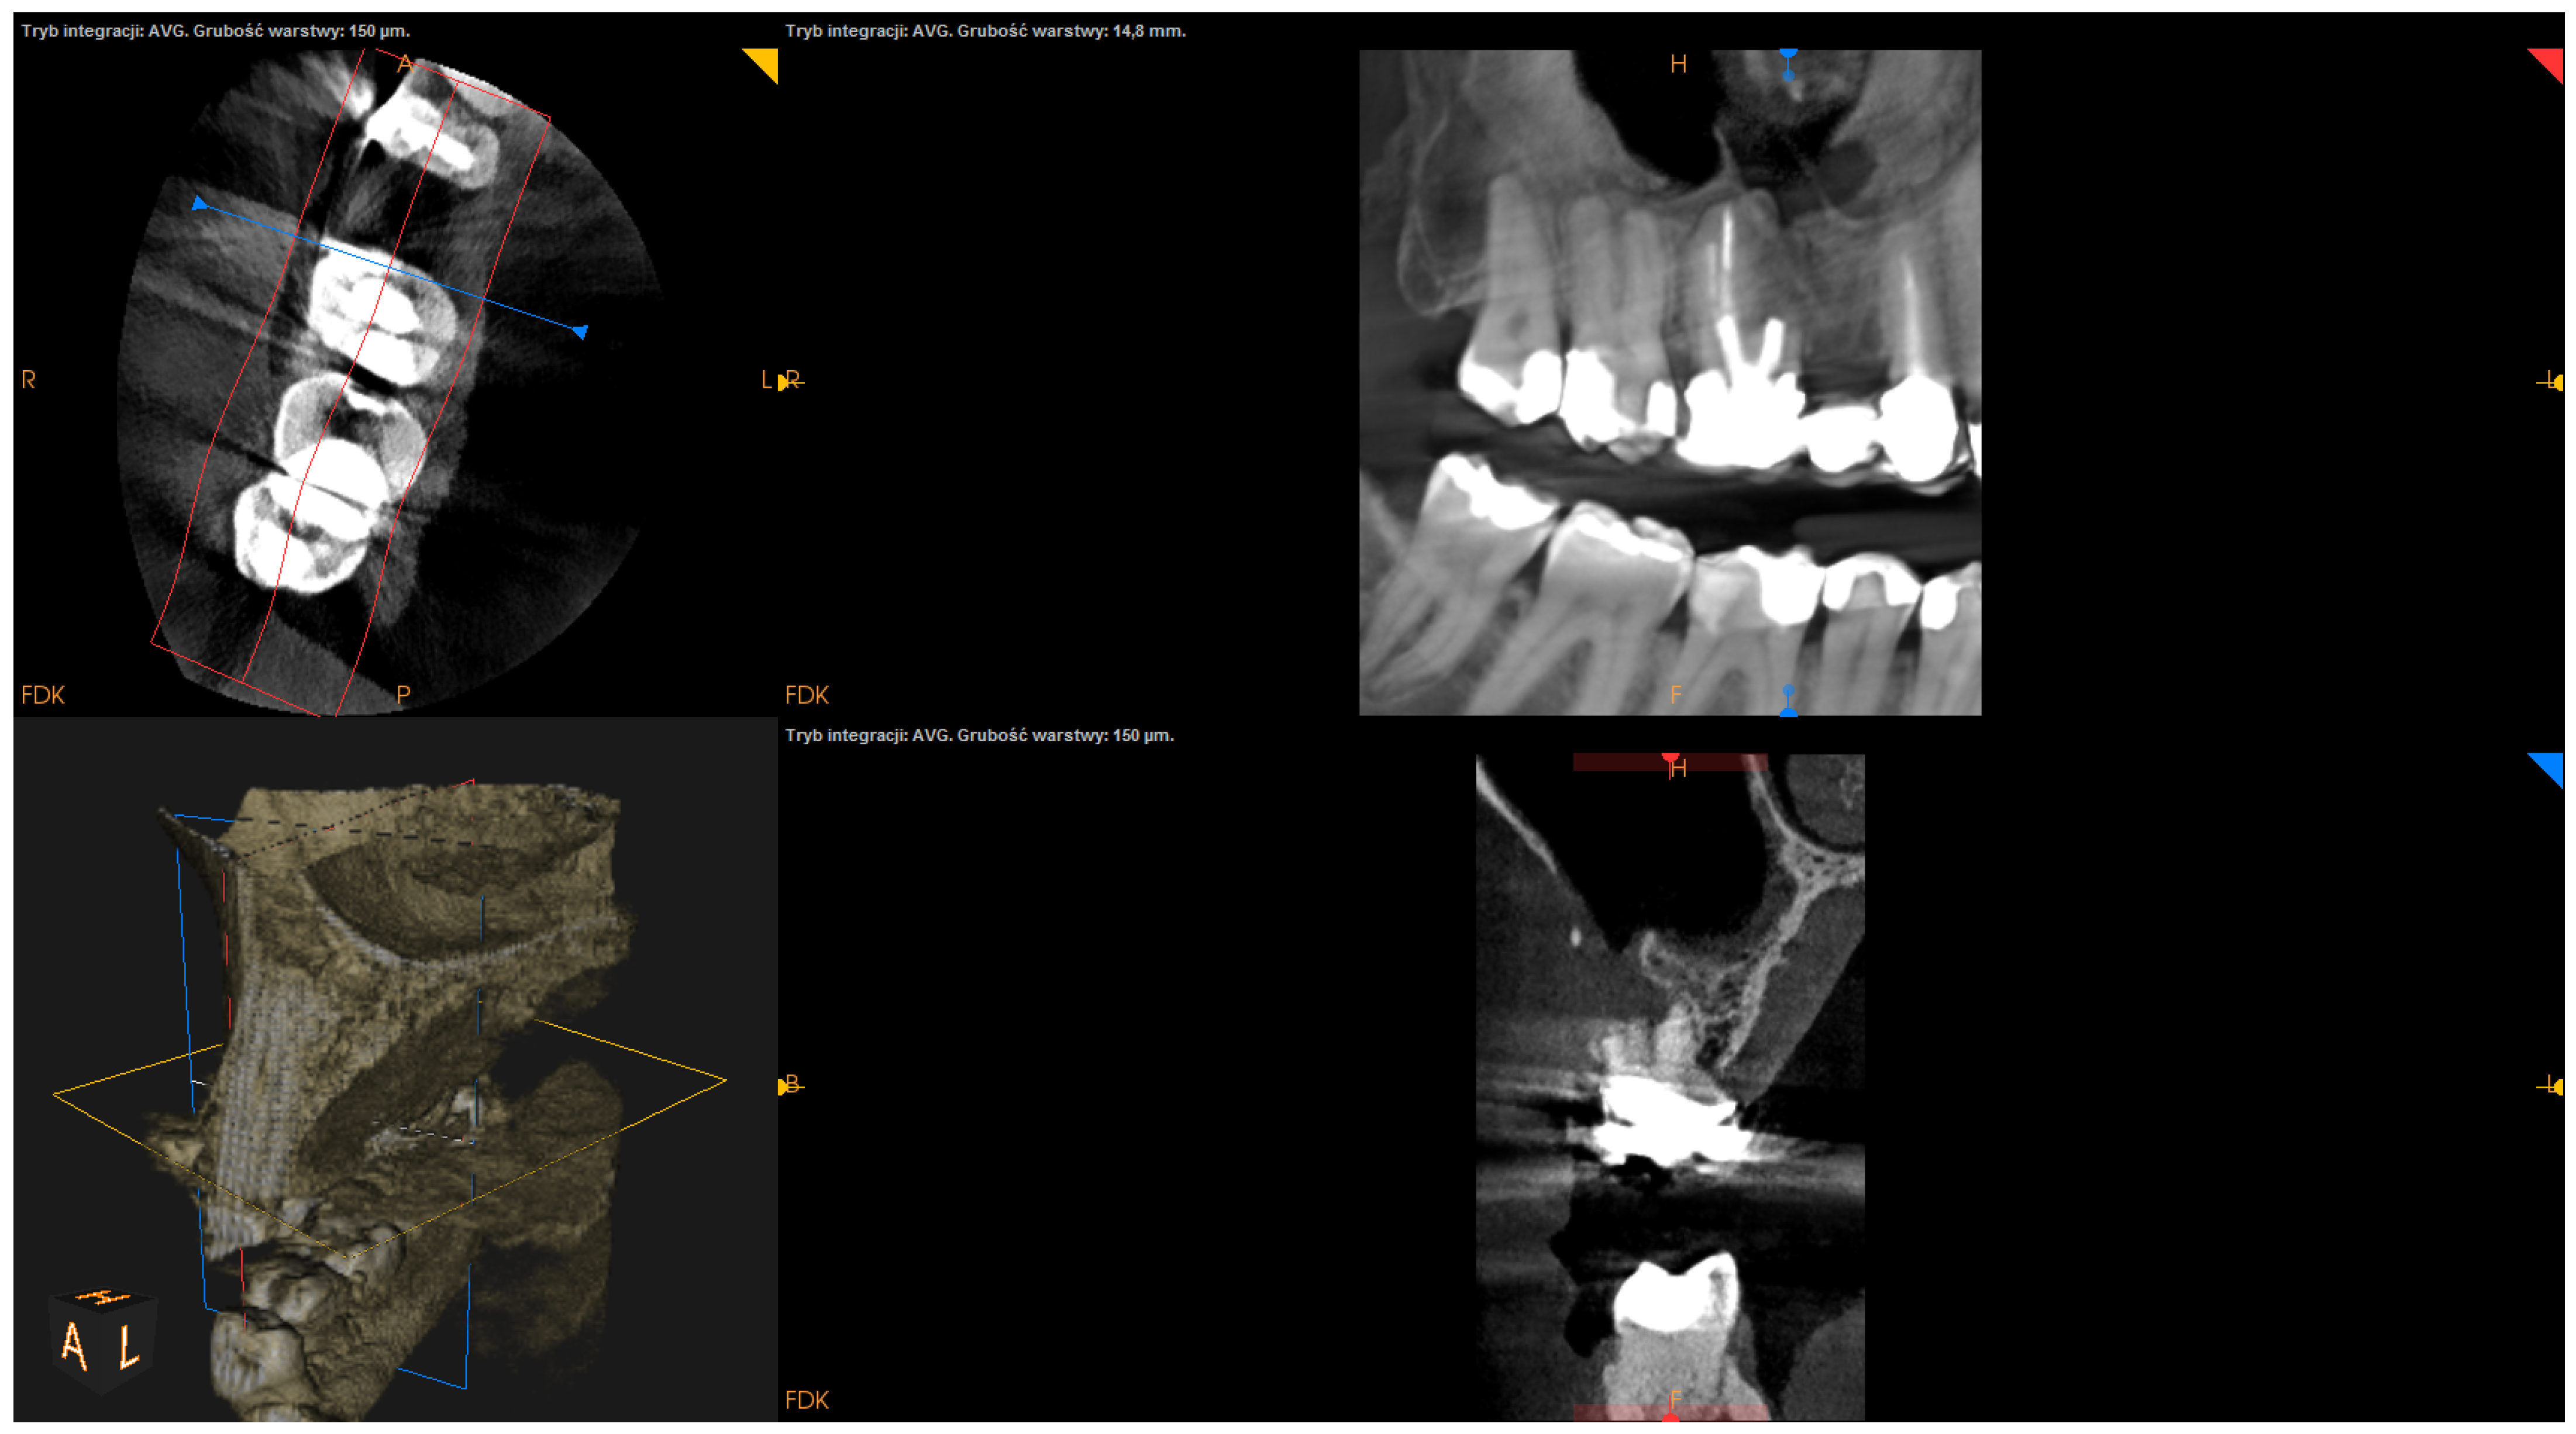

- The status of radiographic healing (rated in all sections, according to modified PENN 3D criteria [28]) was classified as complete healing (Figure 1), incomplete healing (Figure 2), uncertain healing (Figure 3), or unsatisfactory healing (Figure 4).

Figure 4. CBCT image (CS 8100 3D Carestream Dentalⓡ) example of unsatisfactory healing based on PENN 3D criteria. Non-English annotations present software technicalities (AVG integration mode and layer thickness).